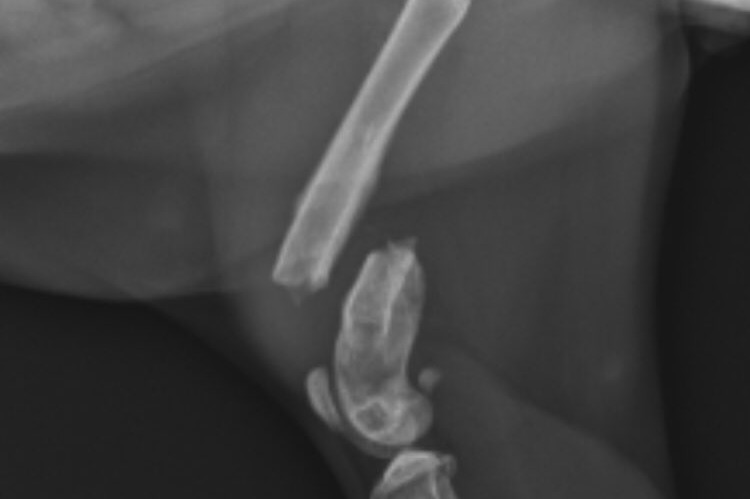

Linus has a CCL tear (think of an ACL injury in humans) that requires surgery. We were going to wait to do the surgery & keep him on pain meds until I can get more student loan money in January, but the instability in his joint has caused him to also break his distal femur. The surgery originally required an orthopedic specialist, and we could've waited to do it, but now it has turned into a pressing issue. He is in pain and his condition is getting worse, they need to go in and put plates by his fracture & fix the CCL. I can't in good conciseness keep him in pain, so I am trying to find a place with payment plans for him with no luck, as there are not that many places with orthopedic specialists in the area. Linus means the world to me, he has provided comfort & sanity with how stressful vet school is.

He was referred to my university (the veterinary school) because it is a difficult case. The specialists fixed the break but he may have bone cancer or a bacterial infection which means more costs past the ~3.8k estimate. They think the break is more likely due to that than a ligament issue like we originally thought because the bone has weird growths at the break. They sent a culture over to pathology & we will know an answer in 5 business days. I can pay 10% of the total costs at the end monthly with a 1.5% interest rate. Thank goodness for options!

Surgery went well! He got a bone plate inserted w 6 screws, leg & everything fixed up. He’s got a check up for stitches in 2 weeks, a radiograph check up in 4 weeks, & then another radiograph check up in 8 weeks. We need to wait on answers for cancer vs bacteria. Thankfully he’s not in pain anymore w meds.